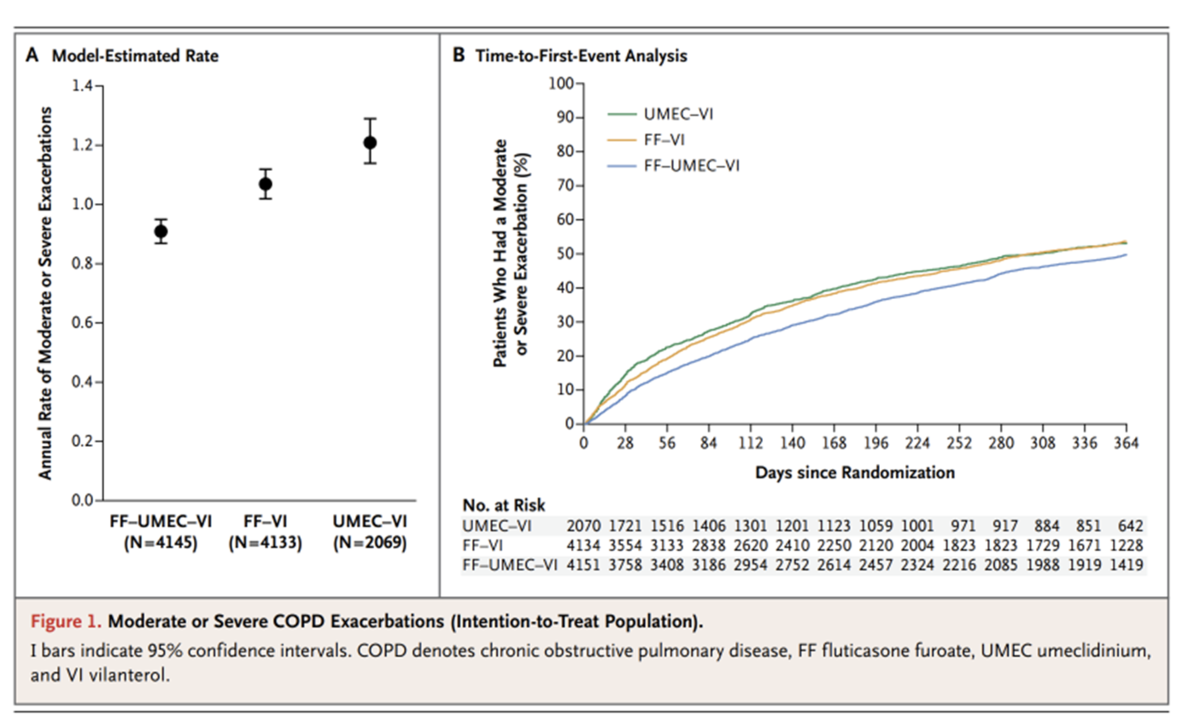

3剤吸入(ICS/LABA/LAMA)に関する最も有名な論文の一つであるIMPACT study (N Engl J Med 2018; 378:1671-1680) を例に挙げて説明します。

そこで、ICS/LABA/LAMA3剤を合剤にして一つのデバイスにまとめてしまい治療した場合どうなるかを検討した試験がIMPACT試験です。がっつりグラクソスミスクラインの支援を受けた試験です。

結果としては、中等症~重症のCOPD増悪が生じる頻度は3剤(ICS/LABA/LAMA)群で0.91/year、ICS/LABA群で1.07/year (HR:0.85 ,95%CI: 0.80-0.95)、LABA/LAMA群で1.21/year (HR:0.75 ,95%CI: 0.70-0.81) であり優位に3剤で増悪頻度は減少したとの事でした。

肺炎の頻度に関しては3剤群で8%、ICS/LABA群で7%、LABA/LAMA群で5%とLABA/LAMAとLABA/LAMA群で肺炎の合併症が低い傾向にあるとの事です。(HR:1.53 95%CI:1.22-1.92; P<0.001) ただ肺炎自体は軽症が多かったとの事です。